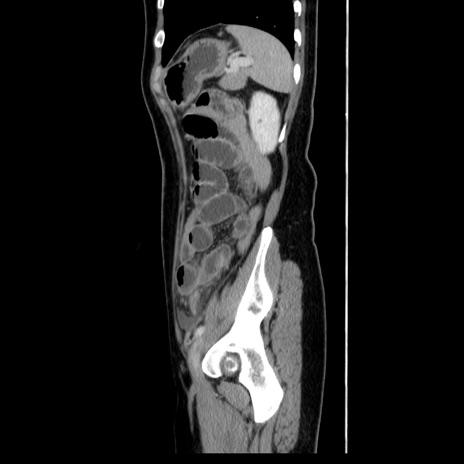

症例39(矢状断像)

【症例】40歳代女性

【主訴】上下腹部痛

【現病歴】2日目から下腹部痛あり。夜間は痛みで眠れなかった。昨日より上腹部痛と下痢が出現。臥位で痛みは軽快したため、休んでいた。本日になって臥位でも立位でも痛みが強くなってきたため救急要請。

【既往歴】子宮内膜症

【身体所見】部:平坦・軟、左上下腹部に圧痛あり、反跳痛あり。

【データ】WBC 21800、CRP 26.78

CT